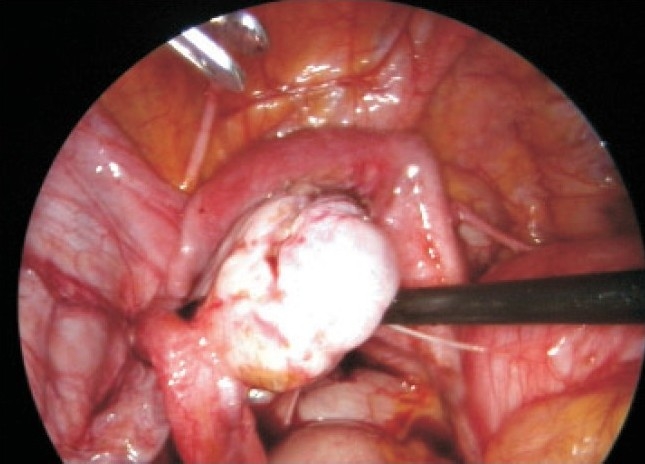

未婚女孩重度痛经,因双侧子宫内膜瘤剖腹手术,经达那唑和GnRHa Depo注射治疗三年多。腹腔镜检查发现她有一个大的、不相通的、功能不全的角伴同侧肾发育不全。腹腔镜下对原始角的切除使疑似子宫内膜异位瘤得到了很大的缓解,这并不是她剧烈疼痛的原因。

An unmarried girl with severe dysmenorrhea had laparotomy for bilateral endometriomas, later treated with danazol and GnRHa Depo injection for more than three years. On laparoscopy she had a large, noncommunicating, functioning rudimentary horn with ipsilateral renal agenesis. Laparoscopic excision of the rudimentary horn gave major relief from the suspected endometrioma, which was not the cause of her severe pain.